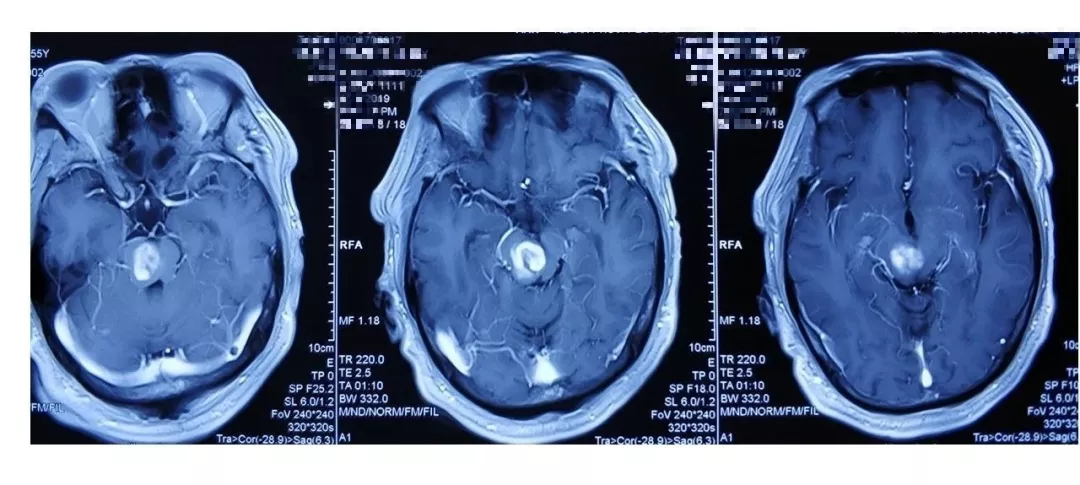

入院后完善CTA,DSA等检查提示颅内多发动脉瘤:

其中右侧颈内动脉眼段动脉瘤(约13.8*14mm大小,瘤颈8.04mm)。和家属沟通病情,告知介入和开颅手术两种治疗方式的风险利弊后,患者家属选择开颅右侧眼动脉段动脉瘤夹闭手术治疗。

进一步行DSA+CT融合,模拟手术入路视角。